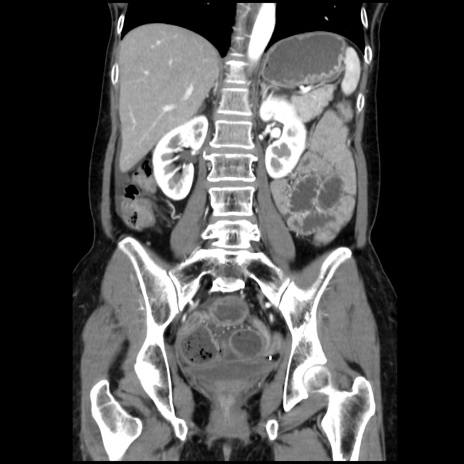

症例32(冠状断像)

【症例】40歳代 女性

【主訴】上腹部痛、嘔気・嘔吐

【現病歴】約9時間前頃から急に上腹部痛、嘔気、嘔吐が出現。改善しないため救急要請。

【既往歴】子宮頚癌(広汎子宮全摘術、放射線療法)、腸閉塞

【身体所見】腹部:平坦、軟、腸雑音亢進、上腹部を中心に腹部全体に圧痛あり。

【データ】WBC 8400、CRP 0.03